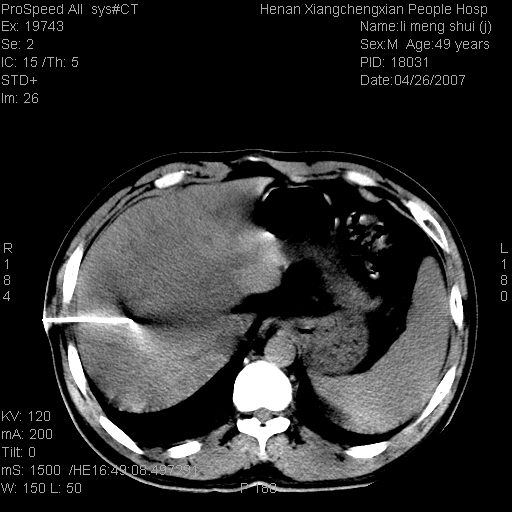

| 患者,男,49岁, 腹疼伴恶心\\呕吐20天,20天前无明显诱因出现右上腹部疼痛,钝疼,无放射,伴恶心\\呕吐,不伴发热.患者不愿增强. b超:肝脏右叶实性占位. ct:肝脏右叶可见一巨块状圆形低密度影,大小约93mm*84mm,其内可见点状高密度影,胆囊、胰腺、脾脏大小、形态及密度未见异常,腹膜后间隙未见肿大淋巴结影。 印象:肝脏右叶巨大肿块,性质待定,建议增强并穿刺活检进一步确诊。 ct平扫: ![]() ![]() ![]() ![]() ![]() ![]() ![]() ![]() ![]() ![]() ![]() ![]() ![]() ![]() ![]() ![]() ![]() 肝脏右叶肿块ct引导下穿刺活检术 患者于16时05分仰卧于ct检查台上,首先行肝脏ct扫描确定进针位置、深度、角度。在局麻下行ct引导下肝脏右叶肿块穿刺活检术。常规消毒、铺巾、局麻。在ct引导下使活检针经右侧腋中线、第9肋间隙垂直胸壁进针90mm,针头进入病变预定位置。在病变预定位置多点、多方向抽取小米样病变组织多块,涂片五张送病理检查。术后穿刺点局部无出血,未出现腹腔积液等并发症。术中及术后患者生命体征稳定,手术于17时10分成功完成。患者安返病房。 穿刺片 ![]() ![]() ![]() ![]() ![]() ![]() ![]() ![]() ![]() ![]() ![]() ![]() ![]() ![]() ![]() ![]() 病理结果肝细胞癌 ![]() 原贴地址:http://www.radinet.com.cn/forum_view.asp?forum_id=4&view_id=24130 ok |